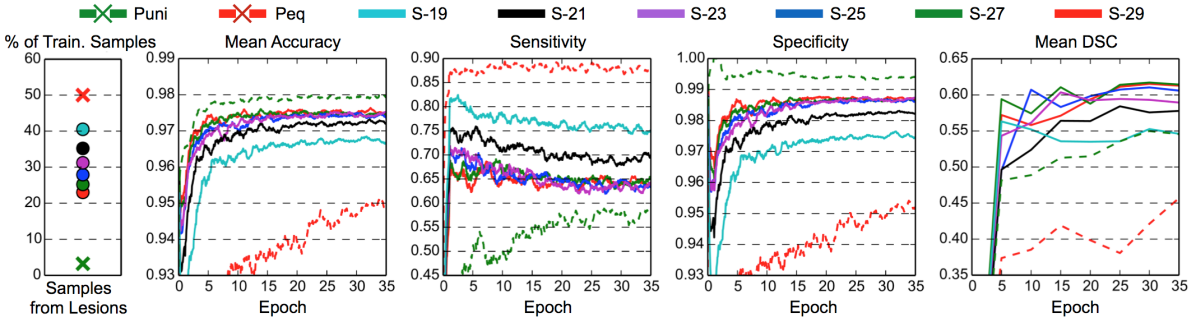

We compare our proposed dense training method with two other commonly used training schemes on the 5-layers baseline CNN (see Fig. 2). The first common scheme trains on patches extracted uniformly from the brain region, and the second scheme samples patches equally from the lesion and background class. We refer to these schemes as P and P. The results shown in Fig. 6 show a correlation of sensitivity and specificity with the percentage of training samples that come from the lesion class. P performs poorly because of over-segmentation (high sensitivity, low specificity). P has better classification on the background class (high specificity), which leads to high mean voxel-wise accuracy since the majority corresponds to background, but not particularly high DSC scores due to under-segmentation (low sensitivity).

To evaluate our dense training scheme, we train multiple models with varying sized image segments, equally sampled from lesions and background. The tested sizes of the segments go from upwards to . The models are referred to as “S-”, where is the side length of the cubic segments. For fair comparison, the batch sizes in all the experiments are adjusted to have a similar memory footprint and lead to similar training times as compared to training on Puni and Peq222Dense training on a whole volume was inapplicable in these experimental settings due to memory limitations but was previously shown to give similar results as training on uniformly sampled patches (Long et al. (2015)).. We observe a great performance increase for model S- over P. We account this partly to the efficient increase of the effective batch size ( in Eq. (4)), but also to the altered distribution of training samples. As we increase the size of the training segments further, we quickly reach a balance between the sensitivity of Peq and the specificity of Puni, which results in improved segmentation as expressed by the DSC.

The segment size is a hyper-parameter in our model. We observe that the increase in performance with increasing segment size quickly levels off, and similar performance is obtained for a wide range of segment sizes, which allows for easy configuration. For the remaining experiments, all models were trained on segments of size .